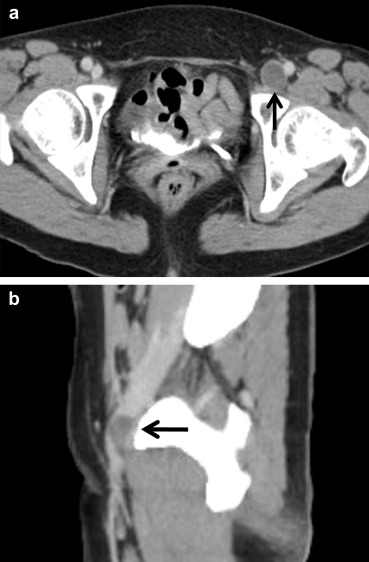

A 50-year-old woman presented with a 1-month history of unexplained edema in the left lower leg. The circumference of the right thigh was 3 cm larger than that of the contralateral side at the mid-thigh level. On the day of admission, her serum D-dimer level was normal (0.26 mcg/mL), but ultrasound examination revealed the presence of an anechoic focal mass, measuring approximately 3.2 cm × 1.7 cm, in the left CFV without compressibility (Fig. 1). A contrast-enhanced computed tomography (CT) scan also showed the presence of an intraluminal low-attenuating mass lesion (2.7 cm × 1.8 cm) involving the left CFV (Fig. 2).

Ultrasound longitudinal scan showing the presence of a 3.2 cm × 1.7 cm, ...

Figure 1.

Ultrasound longitudinal scan showing the presence of a 3.2 cm × 1.7 cm, noncompressible, anechoic mass lesion (asterisk) involving the left common femoral vein, and compressing the venous lumen.